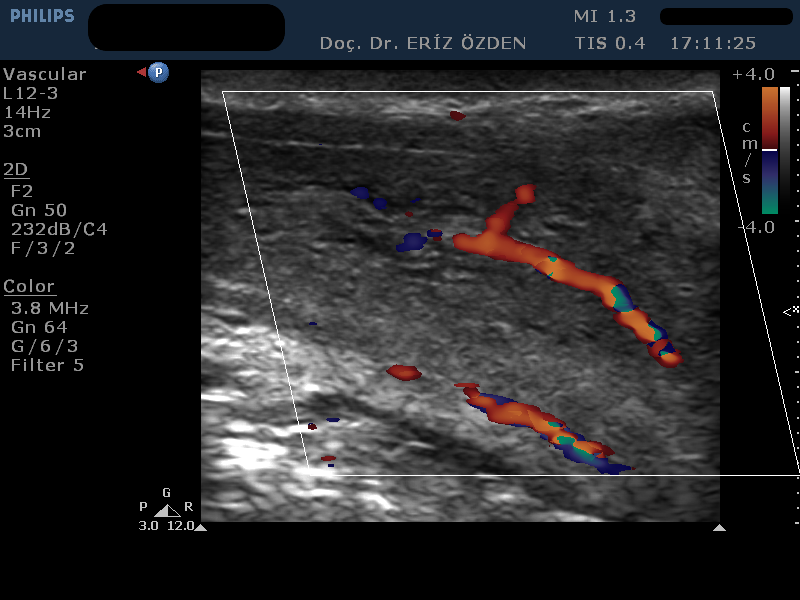

Penil Doppler Nedir? Bu incelemenin tam adı Penil Renkli Doppler Ultrason’dur. Orta ve ileri yaştaki erkeklerde daha sık görülmekle birlikte, bazen genç erkeklerde bile ereksiyon bozukluğu, yani peniste sertleşme yetersizliği görülebilir. Yetersiz sertleşme uzun süre sigara içmiş, yüksek tansiyon ya da şeker hastası erkeklerde daha sık görülen bir rahatsızlıktır. Erektil disfonksiyon adı verilen penisteki sertleşme yetersizliği farklı nedenlere bağlı olarak ortaya çıkabilir. Genç erkeklerde (40 yaş altında) en sık izlenen psikolojik nedenli sertleme bozukluğudur. Daha ileri yaştaki erkeklerde ise testosteron düşüklüğü, atardamarlarda darlık ya da toplardamar yetersizliği nedeniyle yetersiz sertleşme oluşabilir. Penil Doppler tetkikinde, penisin atar ve toplardamarları incelenir. Bu damarların genişliği, damar içinde akan kanın hızı ve penise pompalanan kanın içeride tutulup tutulamadığına bakılır. Böylece, damarsal bir rahatsizlık varsa, tanısı konulmuş olur.

Penil Doppler’de Hangi Ölçümler Yapılır? Normal Değerleri Nedir? Penil Doppler’de atardamardan penis içine akan kanın hızının 35 cm/sn değerinin üzerinde olması gerekir. Ayrıca toplardamarda da kaçak olmamalı, içeri giren kan, penis içinde tutulabilmelidir. Buna end diastolik hız adı verilir ve 0 değerine inmesi, terc,hen ters yönlü akım olarak görülemsi istenir. Bu damar ölçümleri, ilaç verilmesindne önce başlayıp, ilaç verildikten sonra da 30 dakika sürecek şekilde devamlı alınır. Böylece kan akımının dakikalar içindeki değişimi takip edilir. Atardamarların ilaç öncesi ve sonrasındaki çapları da ölçülerek sonuç raporuna yazılır. Ayrıca, sertlik oluştuktan sonra peniste eğrilik gelişirse bunun ölçümleri yapılır. Ek olarak, penisin sertlik derecesi, en sert olduğu andaki uzunluğu ve çapı da ölçülür. Tüm bu ölçüler yazılı raporda belirtilir ve Üroloji doktorunuzun tedavi yöntemini belirlemesinde yön gösterici olur.